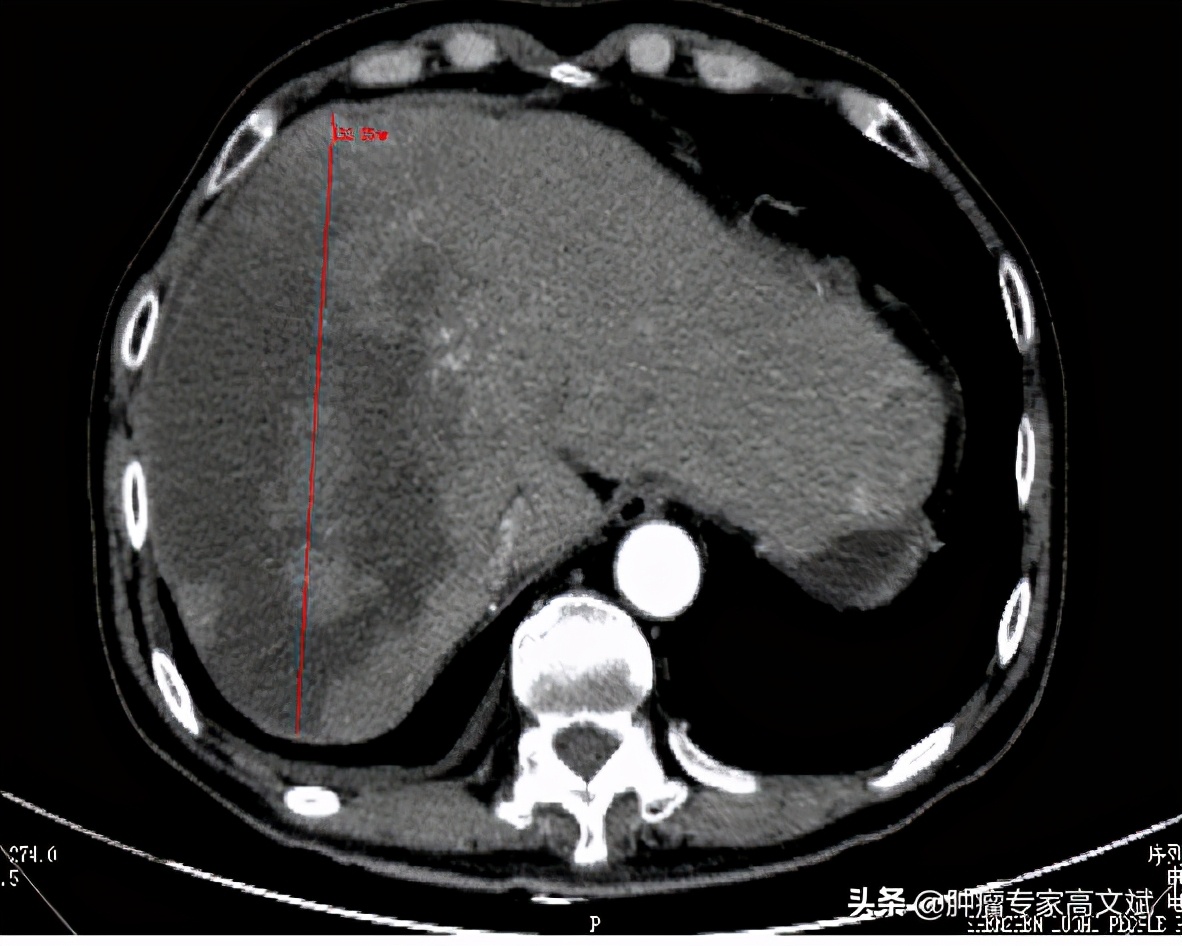

患者老陈今年58岁了,10个月以前在外院发现肝右叶占位,临床诊断为原发性肝癌,由于没有手术治疗的机会,患者在外院实施了一系列的非手术治疗,包括PVL、TACE治疗等,还口服了仑法替尼靶向治疗了2个多月。患者这边的治疗是一刻也没有停,肿瘤那边是生长也一直没有停,就这样患者来我们科的时候,肝右叶肿物较前已经是明显的增大、增多,肝右叶最大的肿瘤已经是16.2cm×10.7cm×9.5cm大小,静脉癌栓也增多,双肺出现了新发转移灶。由于持续性的治疗,患者对于治疗已经失去了信心,只是要求别让他太疼痛即可,茶不思饭不想的他已经不期待什么治疗的疗效了。